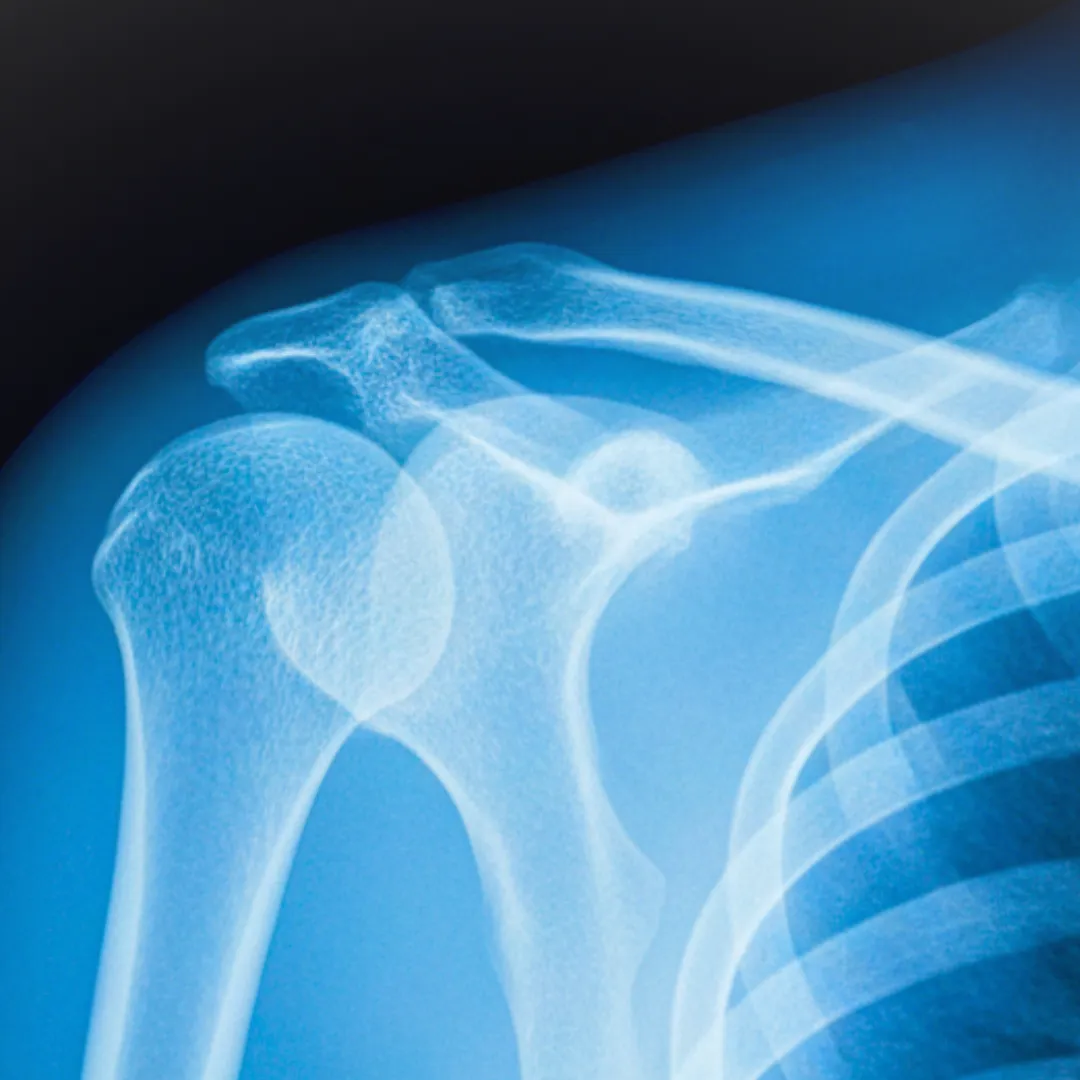

TRAUMATOLOGÍA DE ADULTOS Y GERIÁTRICA

Tratamientos para:

Enfermedades degenerativas

Dolor Lumbar

Dolor de Hombro

Fracturas y Luxaciones

Manguito Rotador